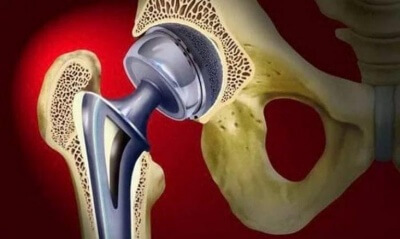

Прочитав эту статью, вы подробно познакомитесь с нашим флагманским продуктом Остеоматрикс - высокоочищенный костный матрикс, полученный из натуральной кости крупного рогатого скота в результате многоэтапного процесса очистки, химической обработки с соблюдением самых жестких норм безопасности. С сохраненными коллагеновым и минеральным компонентами и природной архитектоникой, в соотношении 25% - коллаген и 75% - минеральный компонент кости, аффинно-связанных костных сГАГ не менее 1,5 мг/см3.